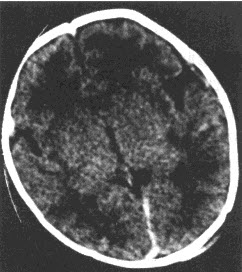

患者,男,73岁。入院诊断:急性阑尾炎并行急诊阑尾切除。术后腹痛症状不改善,不排气、不排便3天。行钡灌肠检查,如图。

(单选题)该患者最可能的诊断是()

E:乙状结肠扭转